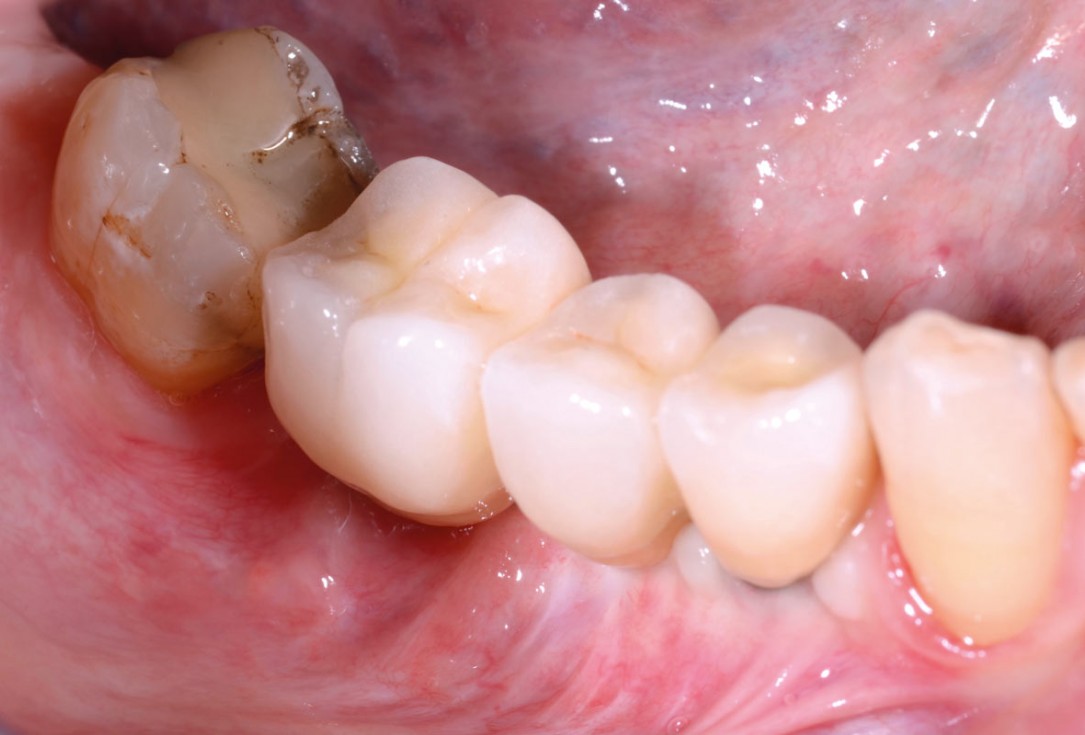

27/29 - Clinical view before installation of the fixed prosthetics, good amount of keratinized tissue around the implantsVertical bone augmentation and broadening of attached gingiva using cerabone®, permamem® and mucoderm® - Dr. R. Naimoli

28/29 - Final prosthetic restorationVertical bone augmentation and broadening of attached gingiva using cerabone®, permamem® and mucoderm® - Dr. R. Naimoli